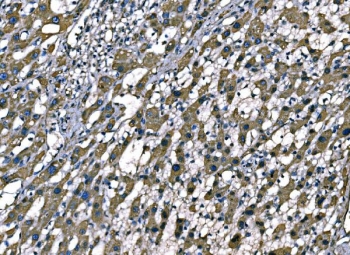

IHC staining of FFPE human liver cancer tissue with Superoxide Dismutase 2 antibody. HIER: boil tissue sections in pH8 EDTA for 20 min and allow to cool before testing.

IHC staining of FFPE human adenocarcinoma of the right colon tissue with Superoxide Dismutase 2 antibody. HIER: boil tissue sections in pH8 EDTA for 20 min and allow to cool before testing.

IHC staining of FFPE human lymphoma tissue with Superoxide Dismutase 2 antibody. HIER: boil tissue sections in pH8 EDTA for 20 min and allow to cool before testing.